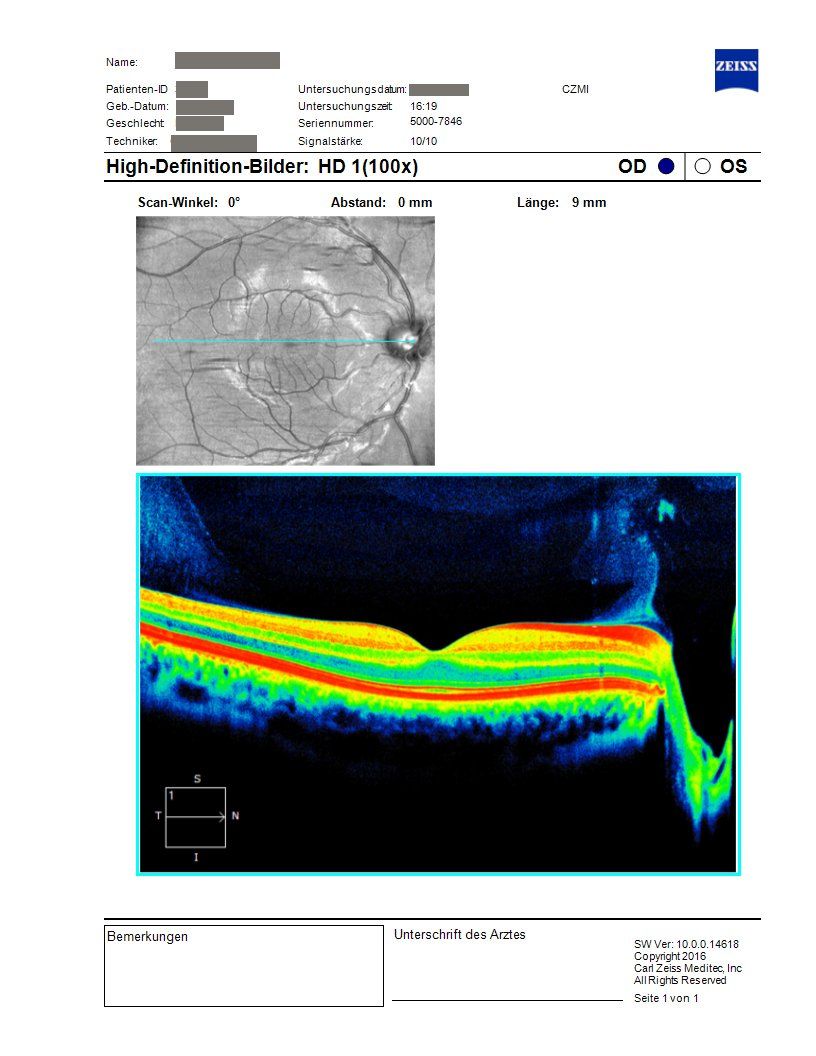

OCT findings of the macula from practice